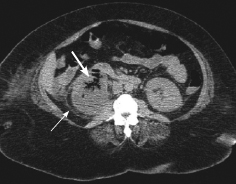

Halima S. Janjua, MD; Rose Ayoob, MD; John David Spencer, MD

Renal artery stenosis is an important cause of surgically correctable hypertension in children.